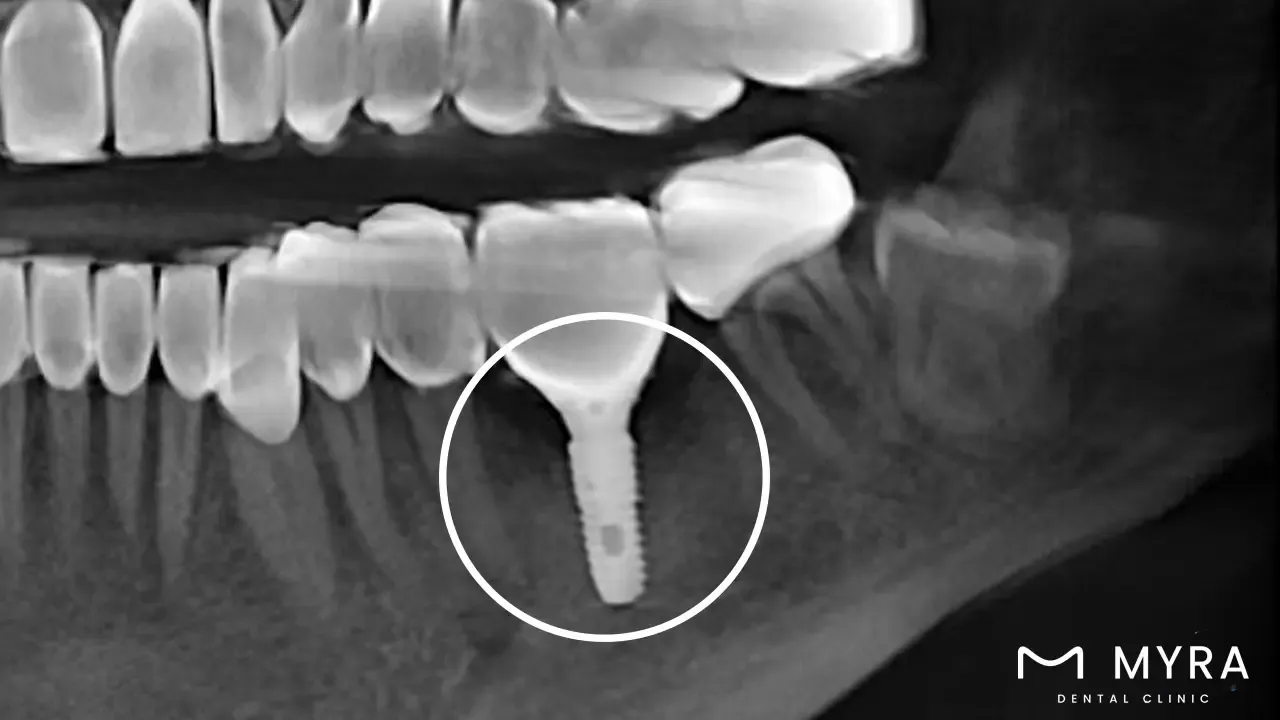

A dental technique known as a single-tooth implant includes using a dental implant to substitute just one lost tooth. The implant is a tiny, screw-shaped post that is medically inserted into the jawbone to act as a synthetic dental crown. It is constructed of biocompatible materials like titanium. It is an anchor that helps as a link where the implant meets the prosthetic tooth or crown and is affixed to the implant after it has combined with the bone.

The fabrication of a functional replacement tooth with a realistic appearance is then completed by attaching a crown or prosthetic tooth affixed to the abutment. A dental practitioner must conduct a thorough examination to decide whether a single-tooth implant is the best option. The crown or prosthetic tooth is next attached once the implant has been surgically placed. Single-tooth implants are regarded as a durable and highly successful method of replacing missing teeth.

There are often multiple processes involved in receiving a single tooth implant. The dental professional evaluates the patient's oral health and knows if they are a good candidate for the procedure. The implant is going to be put into the jawbone through surgery. A procedure that takes place over the following several months is osseointegration, which allows the implant to join the bone.

An abutment is going to be attached to the implant, which helps as a connection between the implant and the artificial tooth, once the implant has fully integrated with the bone. A crown (or artificial tooth) is attached to the abutment, providing a natural-looking and functional replacement tooth.